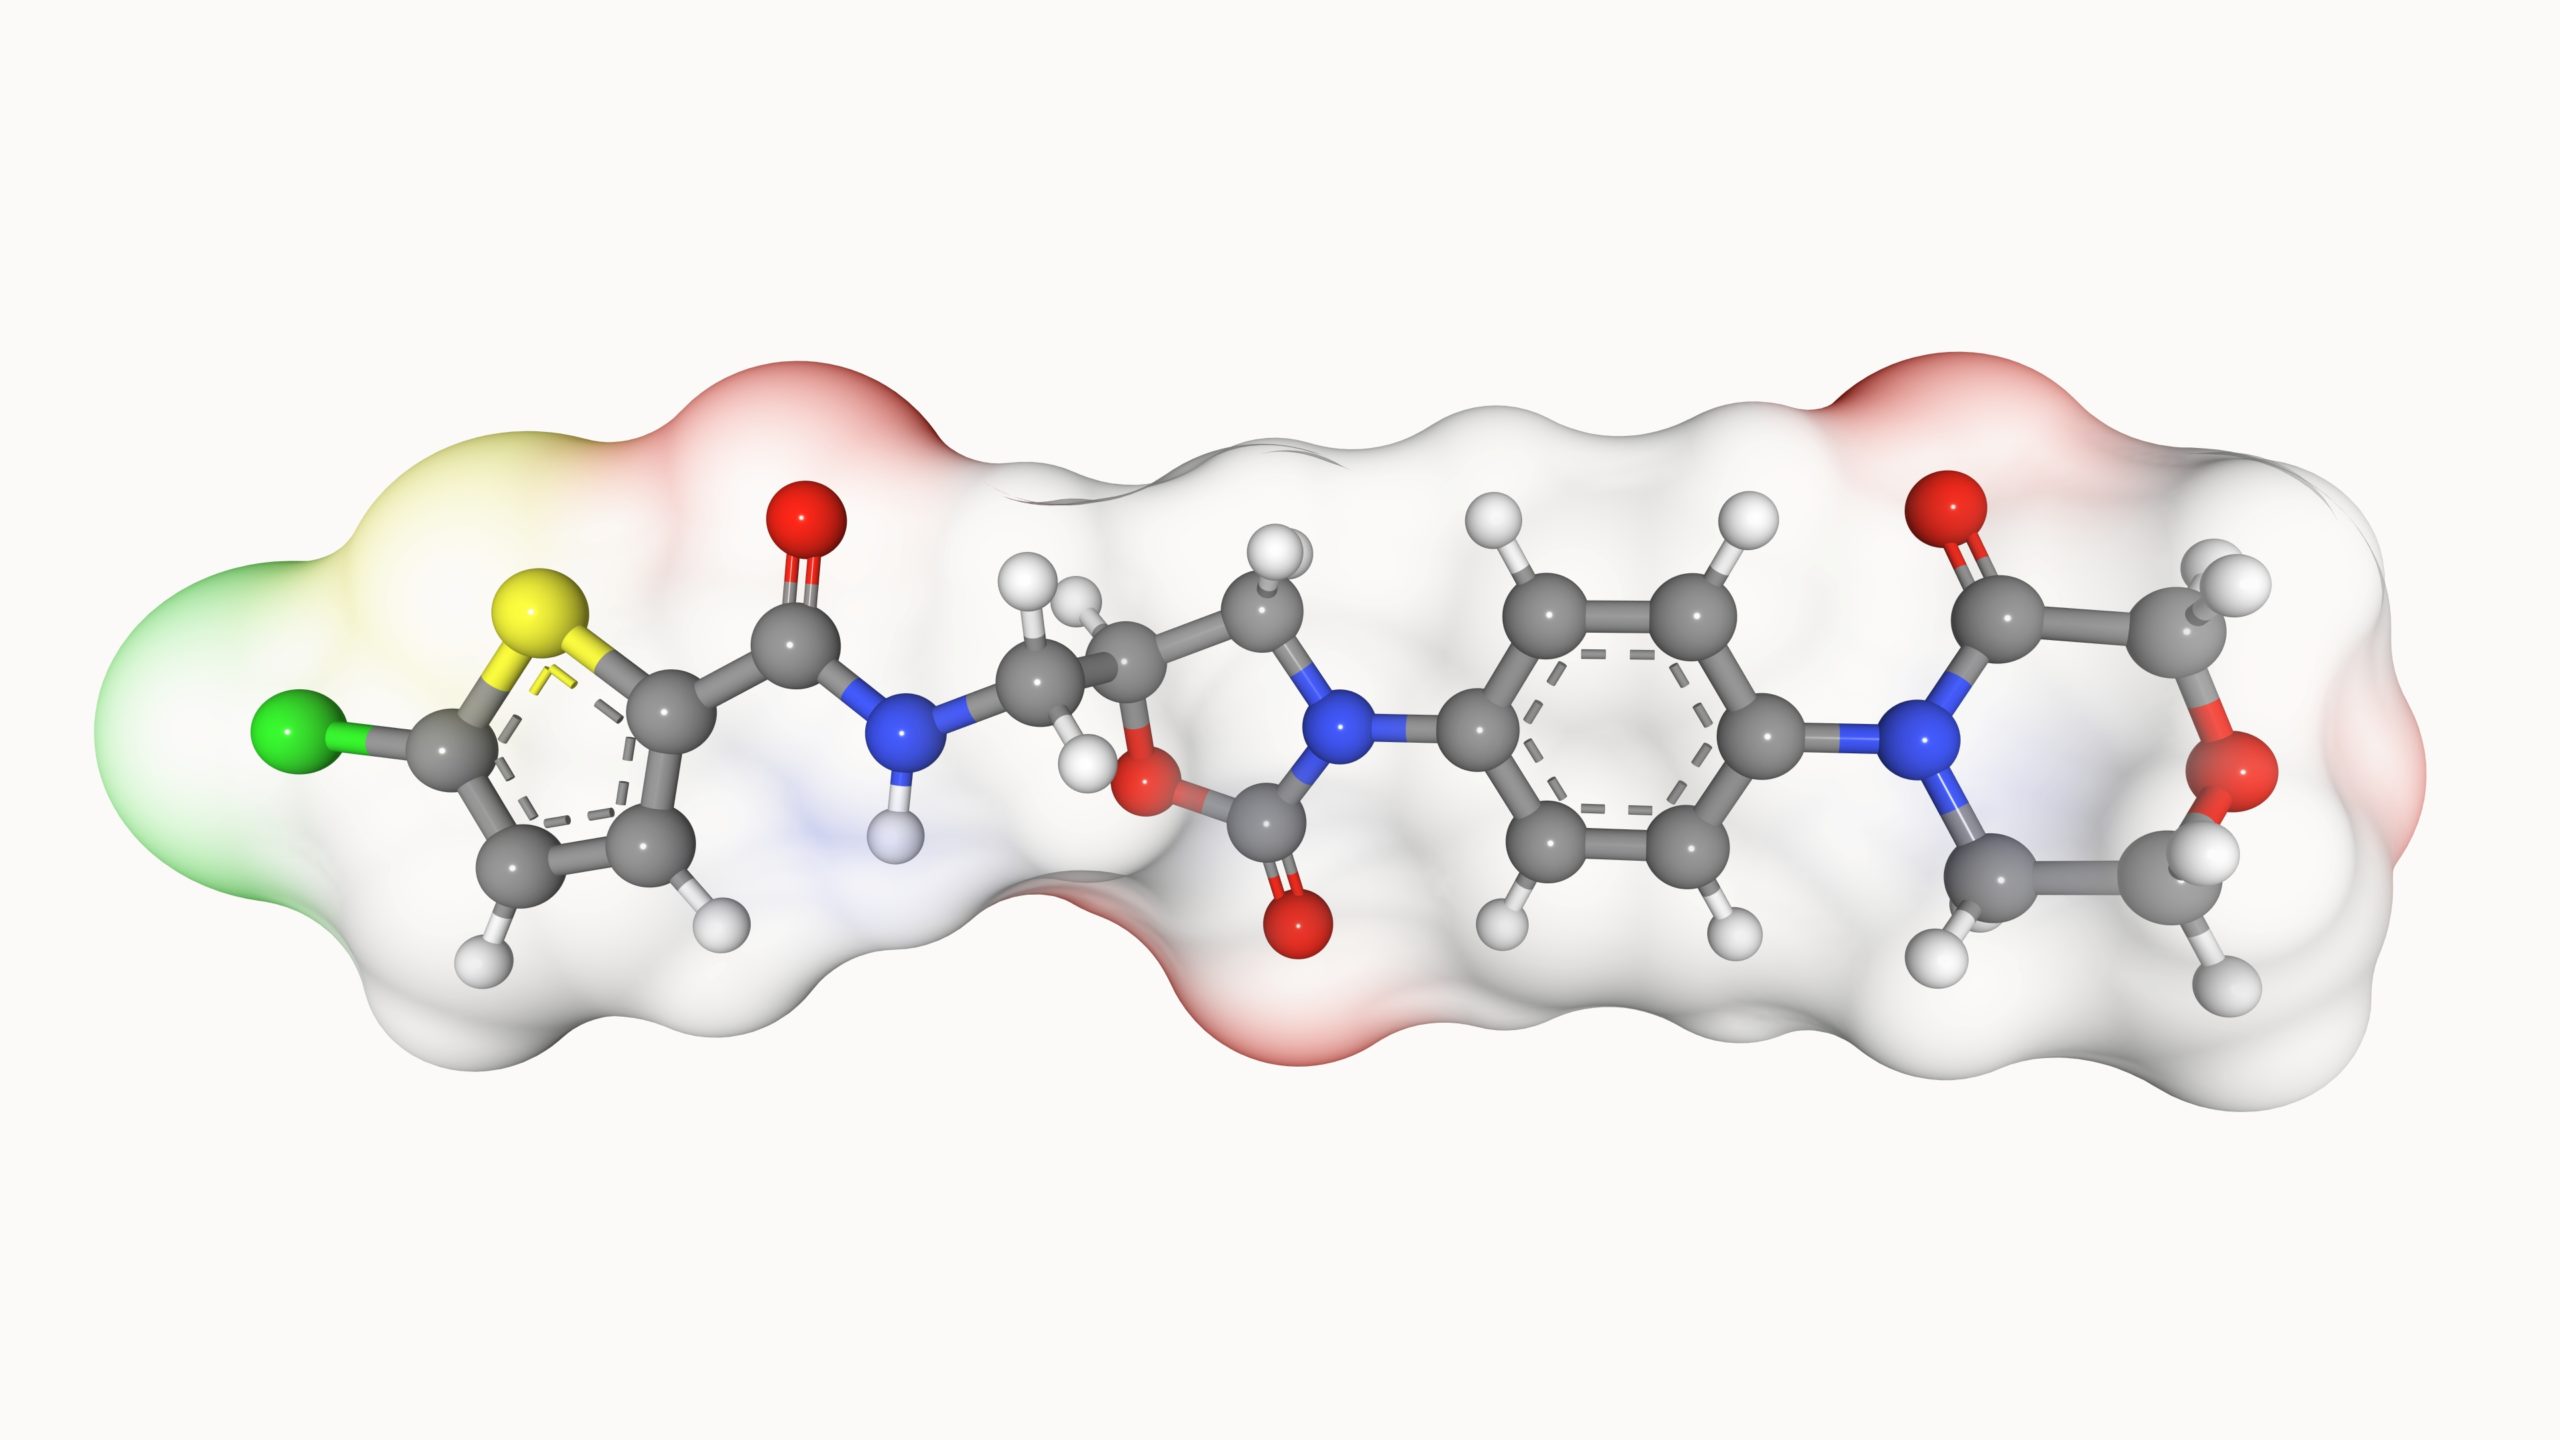

Researchers compared the safety and efficacy of two direct oral anticoagulants (DOACs), apixaban and rivaroxaban, ...Patrick DalyCardiology | February 23, 2023

In a report published in Clinical Cardiology, researchers examined the safety and efficacy of rivaroxaban compared with ...Patrick DalyAtrial Fibrillation | April 7, 2023